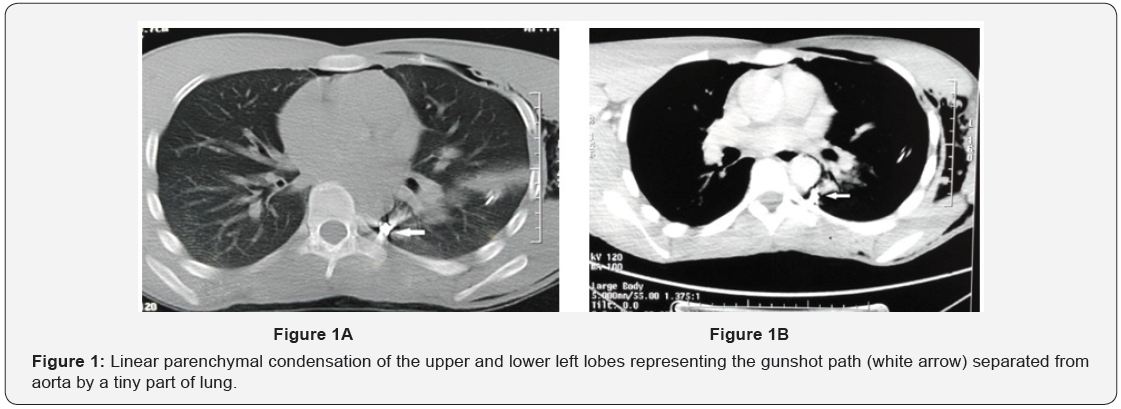

A young man of 23 years old without any past medical history, from a modest socioeconomic family was admitted to the emergency for left axillary gunshot wound that occurred 5 days before. On admission he had stable hemodynamic parameters. He presented severe dyspnea and left thoracic pain. Physical exam revealed an axillary wound inlet of 0.5 cm, sub-cutaneous emphysema and air pleural effusion. There was no outlet. The left radial pulse was present and symmetric to the right. Chest X-ray showed a left abundant hemopneumothorax with the gunshot near aorta. An axillary chest tube was performed and 300 ml of blood was evacuated. Chest CT angiography (Figure 1A & 1B) showed linear parenchymal condensation of the upper and lower

left lobes representing the gunshot trajectory. This gunshot was separated from the aorta by a tiny part of lung. Neither hemomediastinum nor vascular injury was found. Surgery was retained for gunshot extraction. A conservative posterolateral thoracotomy showed blood clots and pachypleuritis. Also, the gunshot crossed the upper left lobe from top to bottom, penetrated the fissure on the side of lower lobe and fitted in the posterior part of the Fowler segment. Removal of the gunshot was performed after resecting a small collar of the lung. Other findings showed nodules on the basal part of left lower lobe which were biopsied. The postoperative course was uneventful. Histology of nodules showed caseo-follicular pulmonary tuberculosis. An antibacillary treatment was prescribed and the patient showed good clinical and radiological evolution (Figure 2).